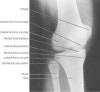

2. A/P Knee View

Demonstrates: femorotibial articulation

Helpful for: Knee Arthritis, Tibial Plateau Fracture, Distal Femur Fracture

Position: supine with cassette under knee and femoral condyles parell to cassette.

Beam directed to point 1-2cm distal to the patella.